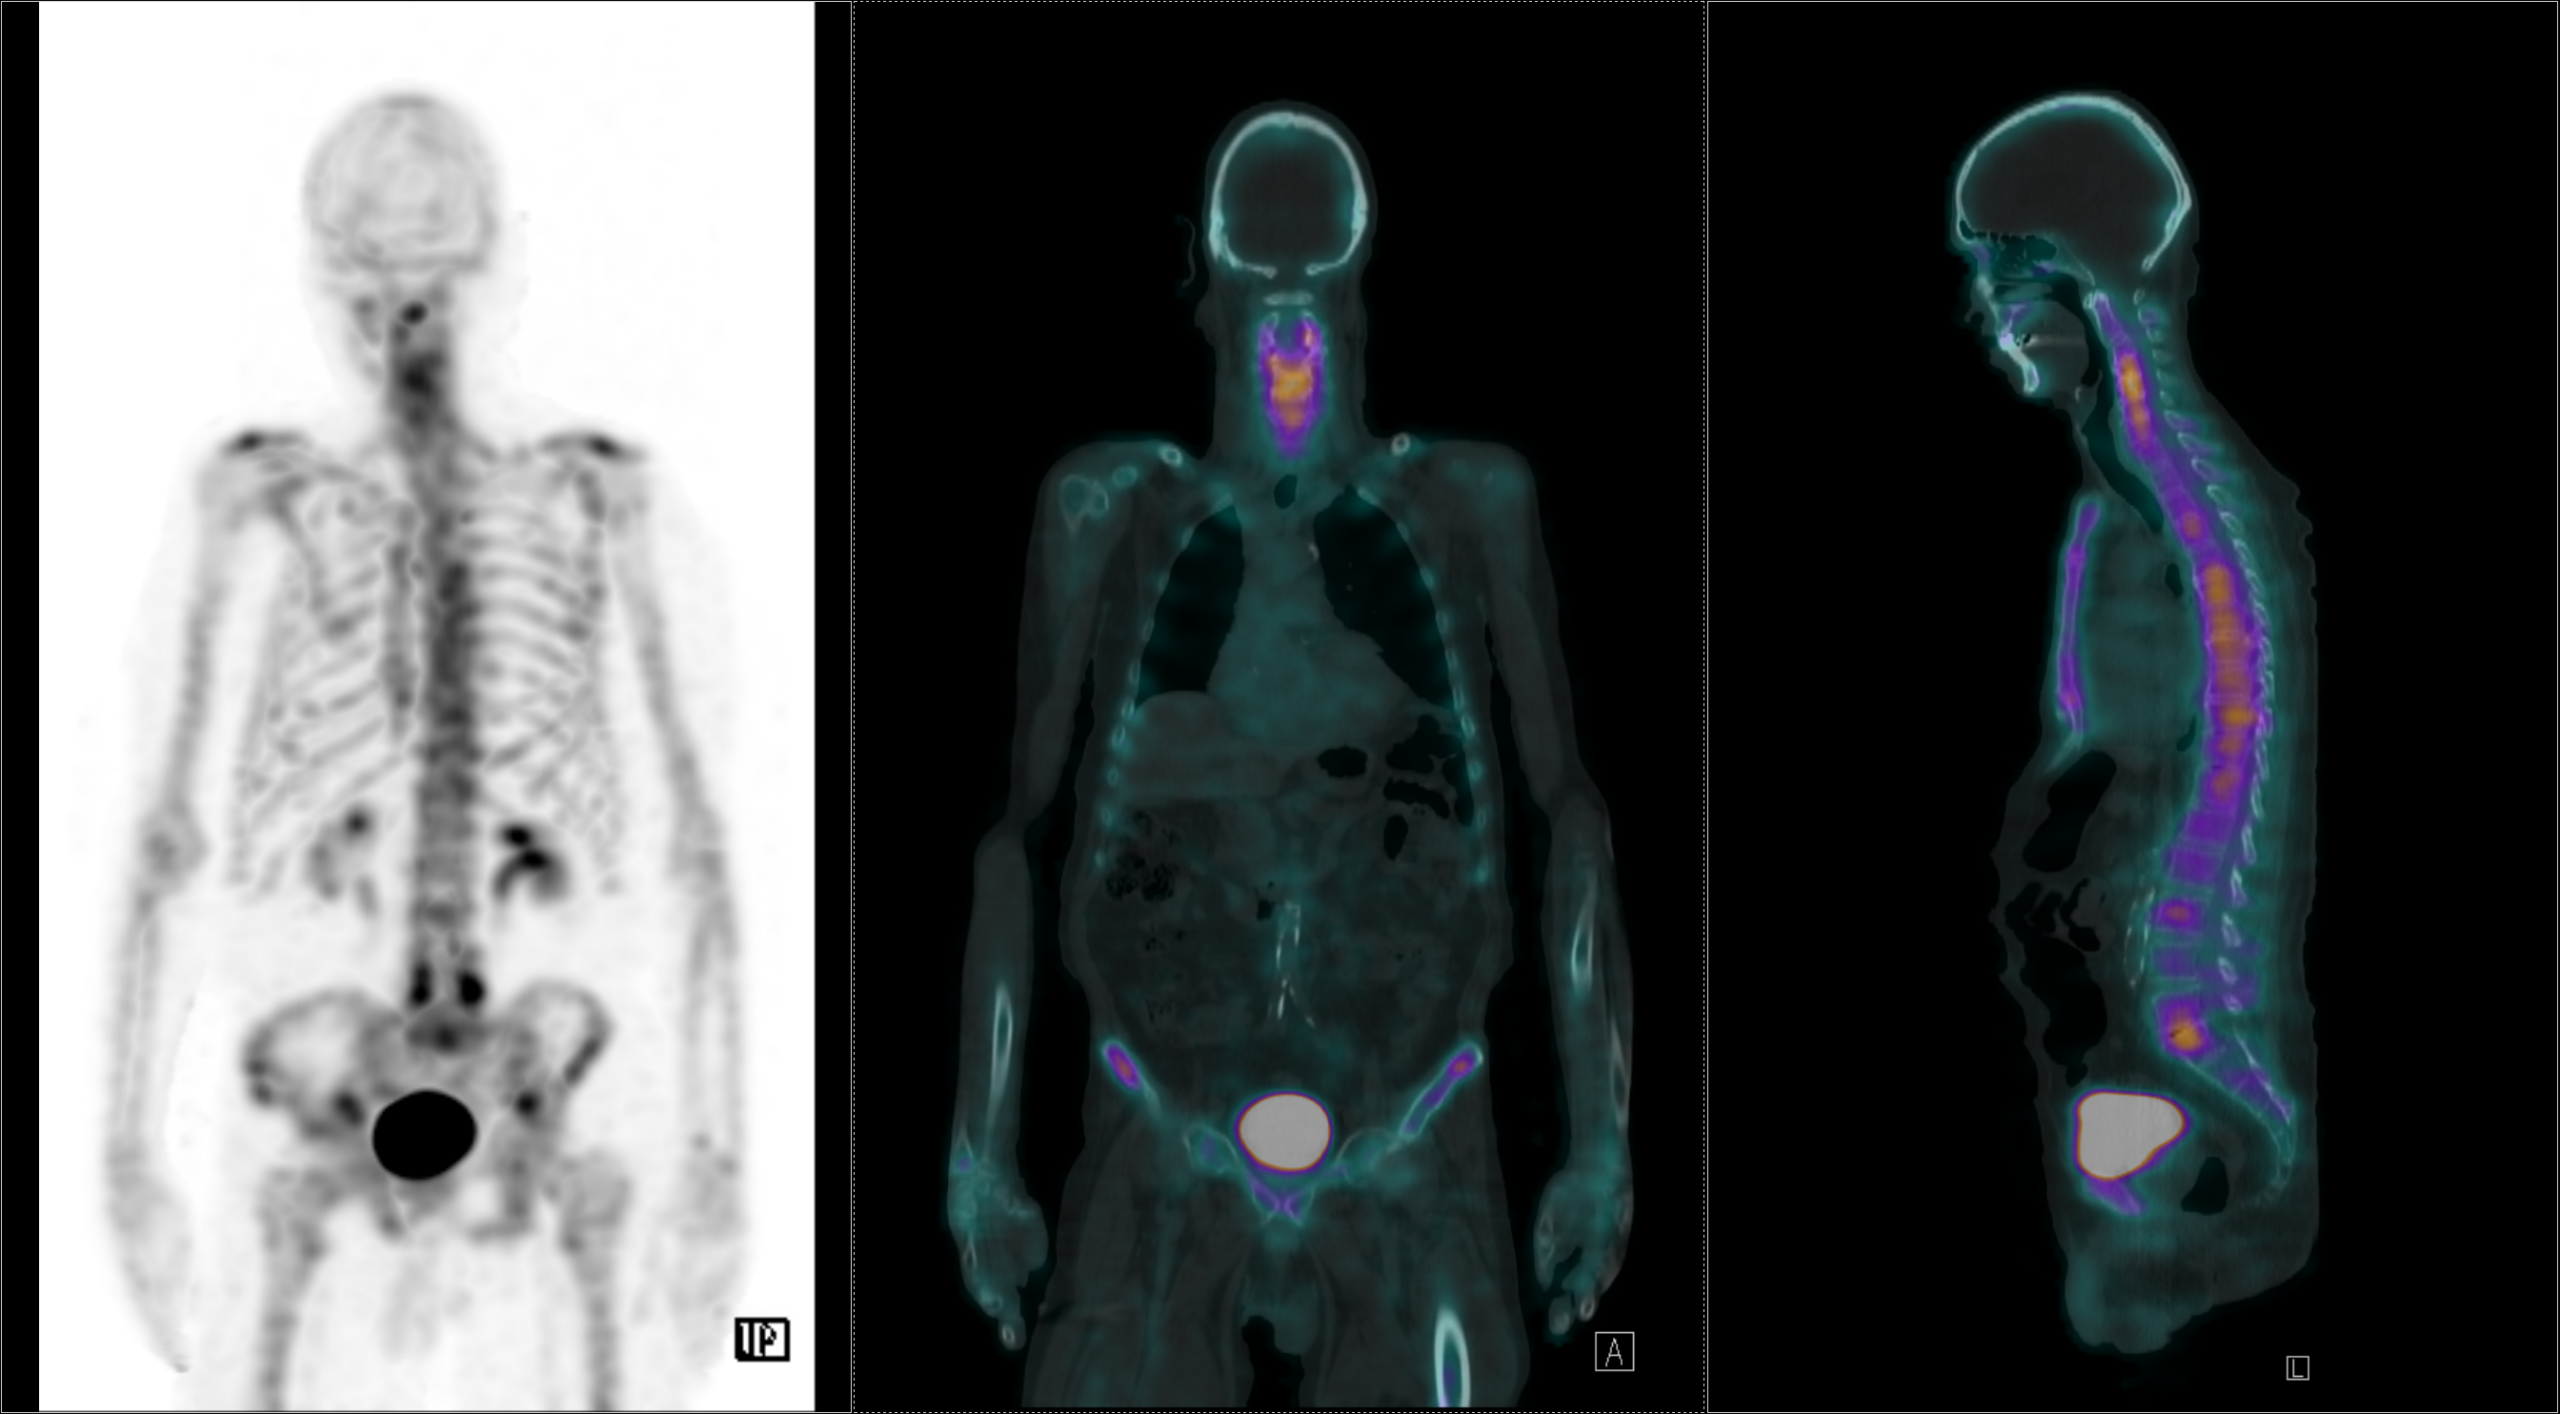

Οι περισσότερες διαγνωστικές εξετάσεις της Πυρηνικής Ιατρικής είναι γνωστές ως σπινθηρογραφήματα, τα οποία στη σύγχρονη εποχή πραγματοποιούνται με τη βοήθεια της γ-κάμερας (γ-camera) ή συστημάτων SPECT/CT, που επιτρέπουν απεικόνιση υψηλής ακρίβειας και λειτουργική ανάλυση σε μοριακό επίπεδο.

Tο Νοσοκομείο ΥΓΕΙΑ είναι το μοναδικό με πάνω από 15 χρόνια εμπειρία στην SPECT CT Aπεικόνιση. Από το 2024 διαθέτει δύο υπερσύγχρονες τομογραφικές γ-κάμερες της Siemens – Symbia Pro.specta SPECT/CT with myExam Companion. Πρόκειται για συστήματα τελευταίας γενιάς που συνδυάζουν υψηλή απεικονιστική ακρίβεια, χαμηλή δόση ακτινοβολίας και πλήρη αυτοματοποίηση της διαδικασίας. Με την χρήση ειδικού σύγχρονου λογισμικού (SIEMENS SYNGO) εξασφαλίζεται η μέγιστη ποιότητα εικόνας. Ειδικότερα οι γ-κάμερες χαρακτηρίζονται από τα εξής:

Όλες οι μελέτες Πυρηνικής Ιατρικής πραγματοποιούνται με SPECT/CT μέθοδο στις 2 υπερσύγχρονες SIEMENS Pro SPecta. Από το δυσδιάστατο στο τρισδιάστατο, από την υπόνοια στη βεβαιότητα.

ΟΛΕΣ ΟΙ ΜΕΛΕΤΕΣ ΜΕ ΤΗ ΔΙΑΓΝΩΣΤΙΚΗ ΥΠΕΡΟΧΗ ΠΟΥ ΠΡΟΣΦΕΡΕΙ Η SPECT/CT ΑΠΕΙΚΟΝΙΣΗ